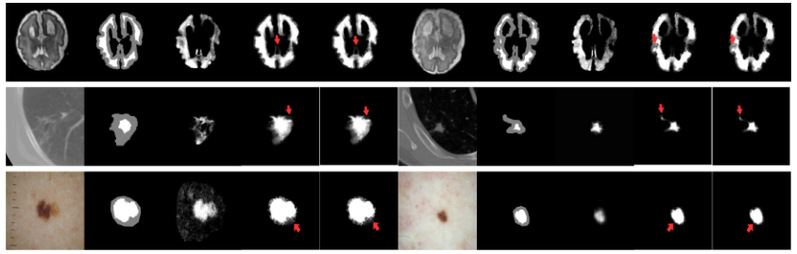

为了验证方法的有效性,研究团队通过将医学图像数据集与和一个自然图像数据集上进行了广泛的实验。医学图像数据集包括:Brain-growth[3], LIDC-IDRI[4], ISIC[5],自然图像数据集包括:AlphaMatting[6]

研究团队在实验三中构建了弱先验测试场景,将该方法与包括深度学习(DIM[7]等)在内的强先验方法以及其他弱先验方法(PDMS[8]等)进行了对比。弱先验测试场景的构建方式如下:从某个特定的医学图像数据集中随机抽取与自然图像数据集等量图像,组成一个新的测试数据集。在进行抠图遮罩预测时,仅提供三分图作为输入。

实验结果表 2表明,在仅提供Trimap的弱先验条件下,微搜索进化优化医学图像抠图算法在均方误差和梯度误差上,优于大多数对比方法。可视化结果(图 4)也显示,该方法能更准确地恢复前景与背景极其相似的模糊边缘区域。

图 4 有无微搜索策略的抠图预测结果可视化对比